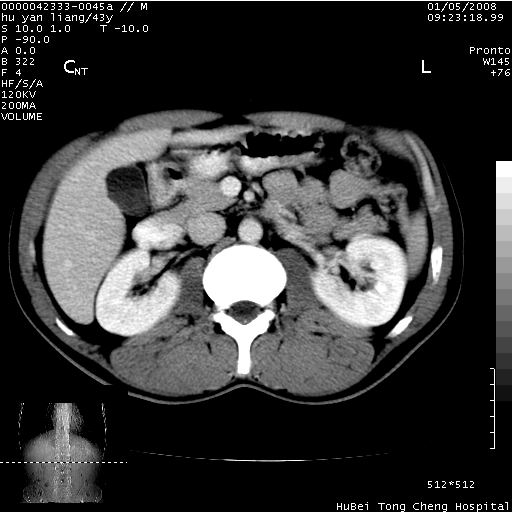

患者 男,43岁。右上腹不适1年余。既往有“肝右叶肝脓肿”病史,经保守治疗后痊愈。

b超提示:1)肝右叶肝内胆管结石。2)肝右叶占位性病变待排。

上中腹部ct轴位平扫+增强扫描(层厚10mm,螺距1.0,重建间隔10mm),图像如下: